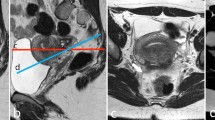

The symptoms can vary according to the type of nodule infiltration: indeed endometrial tissue can directly infiltrate the muscularis propria, lamina propria, or ureteral lumen causing symptoms that may be related to the pelvic endometriosis itself (dysmenorrhea, dyspareunia) or secondary to urinary tract involvement (flank pain, obstruction, and in some cases decline of renal function) [64]. Also in the ureteral endometriosis there are two major pathological types: extrinsic and intrinsic. Extrinsic endometriosis is the most common form (80%) of ureteral involvement and it represents endometrial glandular and stromal tissue within the submucosa and adventitia of the ureter [21]. In addition, scar tissue or fibrosis without true endometriotic invasion of the ureter may also be classified as extrinsic disease. In contrast, intrinsic endometriosis (about 20%) involves the uroepithelial and muscular layer. At MRI, ureteral endometriosis usually appears as hypointense solid nodules on T2W images with spiculated margins, that envelop the ureter, causing dilatation of the ureter upstream [72]. Extrinsic disease may be hypothesized when the interface of fat between the nodule and ureter is no longer visible. MR urographic techniques can be used to obtain three-dimensional reconstructed images from coronal volumetric excretory phase T1W data. The differential diagnosis of ureteral endometriosis includes ureteral invasion by cervical cancer [64].

Uterosacral Ligaments

Uterosacral ligaments (USL) are the most frequent location of deep endometriosis. Bilateral USL involvement is often associated with other posterior deep endometriotic locations, mostly the rectosigmoid colon [81]. At MR imaging normal USL are depicted as thin, regular, semicircular hypointense cords that originate from the lateral aspect of the uterine cervix and the vaginal vault and course dorsocranially toward the sacrum [21]. USL endometriosis is depicted as nodularity within the ligament or as unilateral or bilateral hypointense thickening of the ligament, with regular or irregular margins [21]. The proximal medial portion of the USL is most commonly affected by endometriosis.

According to Bazot et al. thin-section oblique axial T2-weighted sequences (3 mm thick, perpendicular to the long axis of the cervix) can improve the capability of conventional MRI to assess USL endometriosis [81].

Saba et al. suggested that the diagnosis of endometriosis of the USL is simple when ligaments are involved together with the torus uterinus, whereas, when there is only a thickening or an asymmetric nodular irregularity the involvement of the USL can be difficult [64].

In a recently published meta-analysis the sensitivity and specificity of MRI for the diagnosis of endometriosis of USL were 85% and 80%, respectively [82].

Retrocervical Area

The retrocervical area is a virtual extraperitoneal space behind the cervix, located above the rectovaginal septum [21]. It is a common site of deep pelvic endometriosis. Retrocervical implants are often associated with USL involvement and with the retroversion of the uterus [83].

Deep endometriotic lesions of the retrocervical area frequently appear as ill-defined infiltrative tissue, hypointense on T2-weighted images, extending from the posterior uterine serosa to the retrocervical region [21]. Nevertheless, some lesions may contain abundant glandular component and little fibrotic reaction, thus showing high signal intensity on T1-weighted images and variable signal intensity on T2-weighted images [21, 63]. The solid glandular component enhances after intravenous administration of contrast material [63].

Del Frate et al. identified a condition they called ‘‘hourglass-shaped’’ lesions that are found in 25% of cases and are due to posterior extension of a posterior forniceal lesion toward the anterior rectal muscularis. These lesions are usually larger than 3 cm, with a greater risk of extension to the rectal wall [63].

In a recently published meta-analysis the sensitivity and specificity of MRI for the diagnosis of endometriosis of the pouch of Douglas were 89% and 94%, respectively [82].